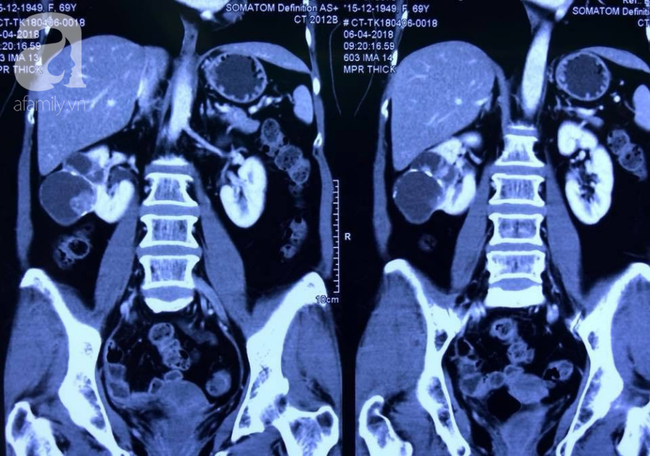

Không an tâm nên lần này, bà quyết định siêu âm để kiểm tra lại tình trạng của nang thận. Sau khi thăm khám trực tiếp, BS quyết định cho bệnh nhân chụp cắt lớp vùng bụng. Kết quả phát hiện khối nang ác tính 5cm ở thận bên phải. Tình trạng này buộc bệnh nhân phải phẫu thuật cắt bỏ khối u nếu không muốn mọi thứ tệ hơn.

BV có Trung tâm Phẫu thuật nội soi xuất sắc đầu tiên tại VN: Cứu người phụ nữ bị ung thư bằng nội soi 3D - Ảnh 2.

Hình chụp CT khối u thận của bệnh nhân.